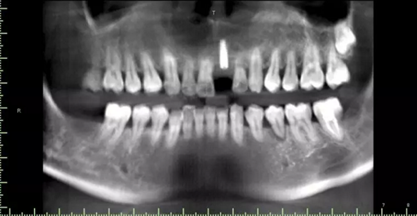

現(xiàn)病史:患者牙周病五年余,牙石(+++)、牙周??;15、26牙齲齒;,今就診我院,要求21牙種植修復(fù)。

1.術(shù)前CT

2.術(shù)前植體設(shè)計(jì)

3.術(shù)前導(dǎo)板設(shè)計(jì)

術(shù)后CT